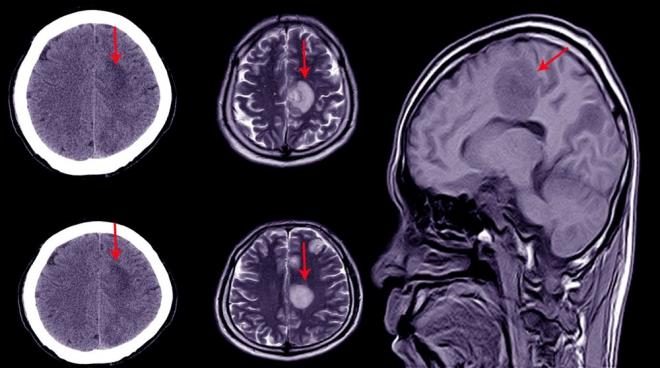

Danimarkalı bilim insanları, felç ve Alzheimer gibi beyin hastalıklarıyla mücadelede devrim yaratabilecek bir çalışmaya imza attı. Araştırmacılar, ilk kez insan beyninden alınan bir parçayı 12 saat canlı tutmayı başardı.

1. Ölümcül hastalıklar için yeni ilaçlar ve tedavilerin bulunmasına yardımcı olacak çığır açan bir çalışmada, ilk kez bir petri kabında* bir santimetrelik insan beyninin bir parçası canlı tutuldu.    Petri kabı: Petri kabı, biyologların kültür hücreleri için kullandığı basit bir cam veya plastik silindir şeklinde, kapağı olan bir kaba deniliyor.

Ölümcül hastalıklar için yeni ilaçlar ve tedavilerin bulunmasına yardımcı olacak çığır açan bir çalışmada, ilk kez bir petri kabında* bir santimetrelik insan beyninin bir parçası canlı tutuldu. Petri kabı: Petri kabı, biyologların kültür hücreleri için kullandığı basit bir cam veya plastik silindir şeklinde, kapağı olan bir kaba deniliyor.